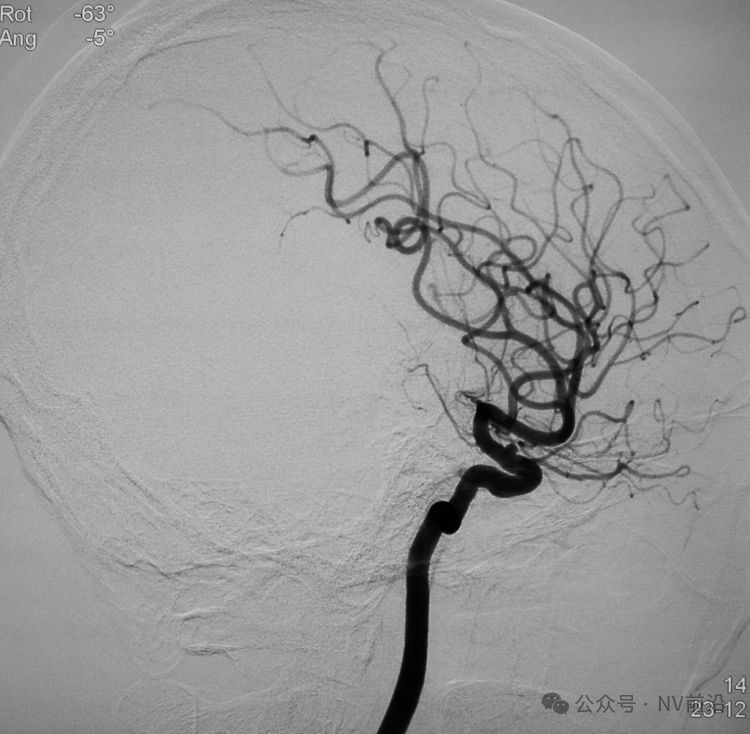

术后右椎动脉工作位造影,

以及正位造影显示动脉瘤完全栓塞,载瘤动脉畅通。